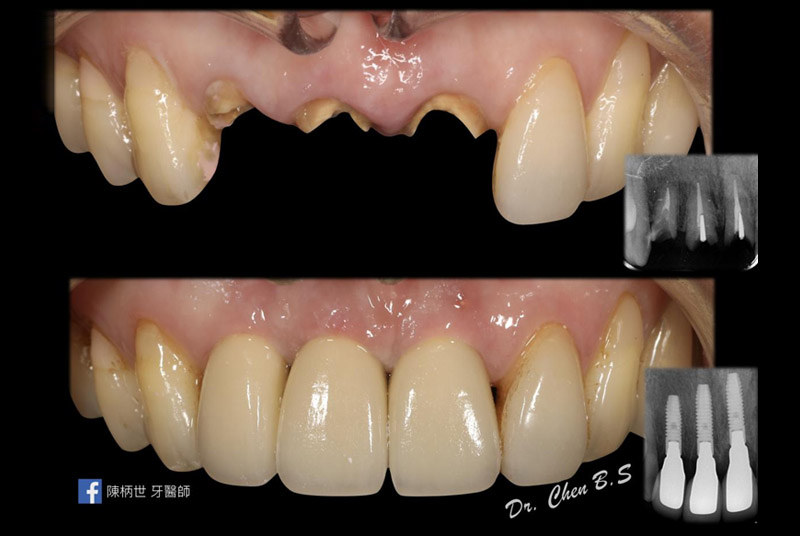

爵世牙醫由院長陳醫師領軍,擁有多年微創植牙與全口重建經驗,並多次赴美國UCLA、紐約大學、鳳凰城,以及韓國、日本進修,將國際最新的植牙趨勢與數位設備導入診所。診所牙醫團隊均接受專業牙科訓練與擁有豐富臨床經驗,從初診檢測、植牙手術規劃到術後追蹤,皆秉持高標準醫療品質,讓每位患者獲得穩定、安全的治療體驗。

傳統植牙多依賴醫師經驗,手術風險與誤差相對較高。為了讓患者享有更精準與安全的植牙體驗,爵世牙醫院長陳醫師引進世界級先進 3shape Trios 數位植牙系統,透過術前完整模擬定位,提供詳實植牙資訊與輔助工具,大幅降低手術風險。

不同於傳統作法,數位微創植牙結合口內掃描與電腦斷層影像,如同飛行員搭配衛星導航般精準,能更精確避開神經、血管與上顎竇,並將誤差控制在約2mm。 此技術特別適用於全口重建與多顆植牙,不僅減少患者手術不適,也能加快恢復速度,讓治療結果更穩定、更安心。

使用通過全球認證的大廠植體,具備優異耐用度與生物相容性,搭配高硬度二氧化鋯牙冠,兼顧美觀與實用性。 - 高精準數位定位